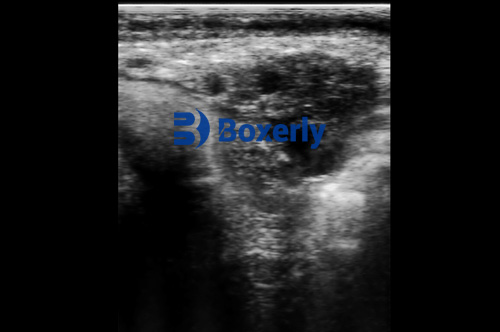

Ovum Pick Up is a minimally invasive procedure used to collect unfertilized oocytes directly from the ovaries of live cows. Under ultrasound guidance, a specialized aspiration needle is inserted through the vaginal wall into the ovarian follicles. The collected oocytes are then matured, fertilized in vitro, and cultured into embryos, which can be transferred to recipient cows or cryopreserved for future use.

One of the most critical advancements in OPU is the use of high-frequency, high-resolution ultrasound probes. Modern probes, operating at frequencies between 7.5 to 10 MHz, provide detailed images of ovarian structures, allowing precise follicle targeting. Improved imaging minimizes trauma to ovarian tissue, increases the retrieval of viable oocytes, and reduces procedure time.